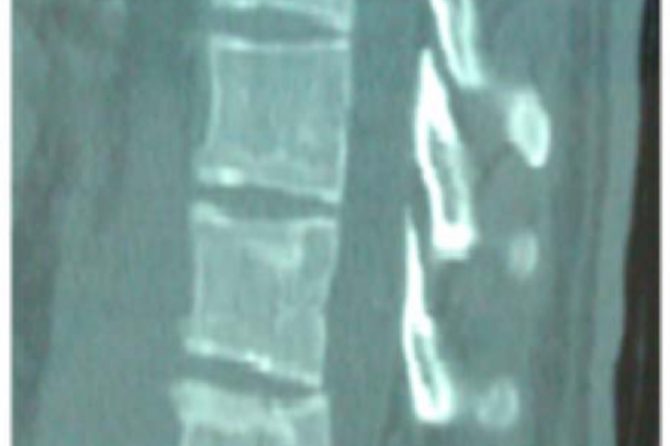

Upon admission, palpation revealed tenderness at the thoracolumbar region. His neurologic examination was normal with no motor or sensory deficit of the lower and upper limbs. Ultrasonography was performed to exclude blunt abdominal concomitant injuries. Simple radiographic evaluation of the cervical spine, thorax and pelvis did not demonstrate associated injuries. Radiographs (Figs. 1, 2) and CT scans (Fig. 3) of the thoracolumbar spine revealed a transverse fracture at the level of T12. The CT scan further demonstrated a split of the posterior elements, progressing anteriorly into the vertebral body. Conservative treatment was decided and the patient, following an initial period of bed rest, was mobilized wearing a thoracolumbar orthosis. Appropriate antithrombotic prophylaxis with low molecular weight heparin was administered, until full ambulation was achieved. The patient was followed up with serial thoracolumbar radiographs for the first 6 weeks of ambulation and later on, in one month intervals. The thoracolumbar orthosis was applied for three months. At the 5th month follow-up, he was pain free with radiographic signs of mild vertebral kyphosis. Upon completion of treatment, he returned successfully to pre-injury levels of daily activity, without any impairment.

Fig. (3). CT scan – sagittal plane, demonstrating the same T12 fracture shown in the radiographs.